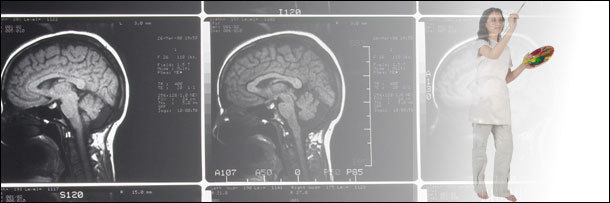

Your Personality Is Determined by Your Left or Right Brained-ness

If you have functioning ears, you've definitely been told at some point in your life that lefties can access some cerebral cheat code that makes them artistically talented or emotional, and that righties are better at logical or intellectual thought. And it's all because the right side of your brain (which controls the left side of your body) is totally in charge of your creativity, while the left side controls your logic.

The Truth:

It turns out that the whole thing about creative genius stemming from the right side of your brain is a big fat myth. Yet this myth is so pervasive that teachers are often told to balance the amount of right-brain and left-brain activities, lest their fragile little brains develop into the cognitive equivalent of those arm wrestlers with one giant arm.

The brain does indeed have some specialized structures that handle certain functions, but the idea that they cluster to opposite sides of the brain, like neurolinguistic cliques of nerds and jocks in a high school lunchroom is ridiculous. For example, while things like grammar and word production are both located on the left side of the brain, intonation and emphasis happen on the right. So you're not going to be much good with language if you're not pretty handy with both hemispheres.

Most brain functions work this way. Along with language, emotions (supposedly controlled by the right brain), and arithmetic (supposedly dominated by the cold, calculating left hemisphere) both get the bi-lateral treatment. Scientists will tell you that in order to be truly creative or logical, you need resources from both sides of your brain.

Complicating our vision of the brain as an East Coast/West Coast battle is the fact that sometimes one part of your brain will take over the functions of areas that have been damaged. Which is why people who have had to remove an entire brain hemisphere don't suddenly lose all their "creativity" or "logic" functions. They go on to do things like graduate college, and they usually regain a good chunk of the supposedly lost localized functions.